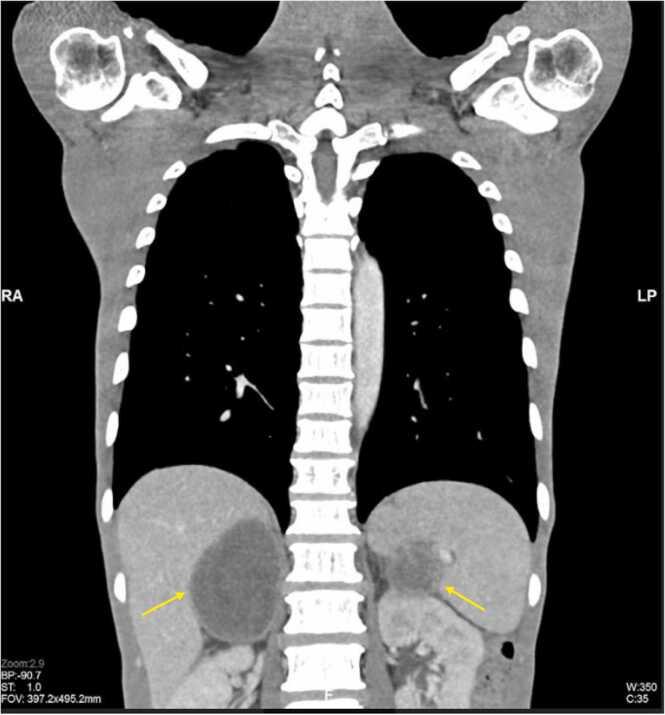

Rhinosporidiosis is one of the granulomatous diseases endemic in Asia, Africa, and Europe, with Southern India and Sri Lanka having the greatest prevalence rates. It is typically understood to affect the upper respiratory system. Involvement of the lungs beyond the trachea is infrequent as compared to the upper respiratory tract. We revealed an uncommon case of disseminated rhinosporidiosis in a diabetic patient, who initially presented with shortness of breath associated with cough and fever. Two months prior to these symptoms, he was having oral ulcer and dysphagia and, subsequently, loss of weight. Chest radiograph and CT thorax revealed military nodules with multiple suppurative neck and mediastinal lymphadenopathy and bilateral adrenal lesions. He was initially investigated for tuberculosis, metastatic malignancy, or lymphangitic carcinomatosis before a biopsy revealed Rhinosporidiosis. Hence, histopathological or laboratory evidence is frequently crucial to back up imaging concerns so the appropriate treatment can be given.

鼻孢子虫病是一种在亚洲、非洲和欧洲流行的肉芽肿性疾病,印度南部和斯里兰卡的患病率最高。通常认为它会影响上呼吸道系统。与上呼吸道相比,气管以外的肺部受累情况并不常见。我们报告了一例糖尿病患者罕见的播散性鼻孢子虫病病例,该患者最初表现为伴有咳嗽和发热的呼吸急促。在出现这些症状的两个月前,他有口腔溃疡和吞咽困难,随后体重减轻。胸部X光片和胸部CT显示粟粒状结节,伴有多个化脓性颈部和纵隔淋巴结肿大以及双侧肾上腺病变。在活检显示为鼻孢子虫病之前,他最初被怀疑患有结核病、转移性恶性肿瘤或淋巴管癌病。因此,组织病理学或实验室证据对于支持影像学诊断至关重要,以便能够给予适当的治疗。